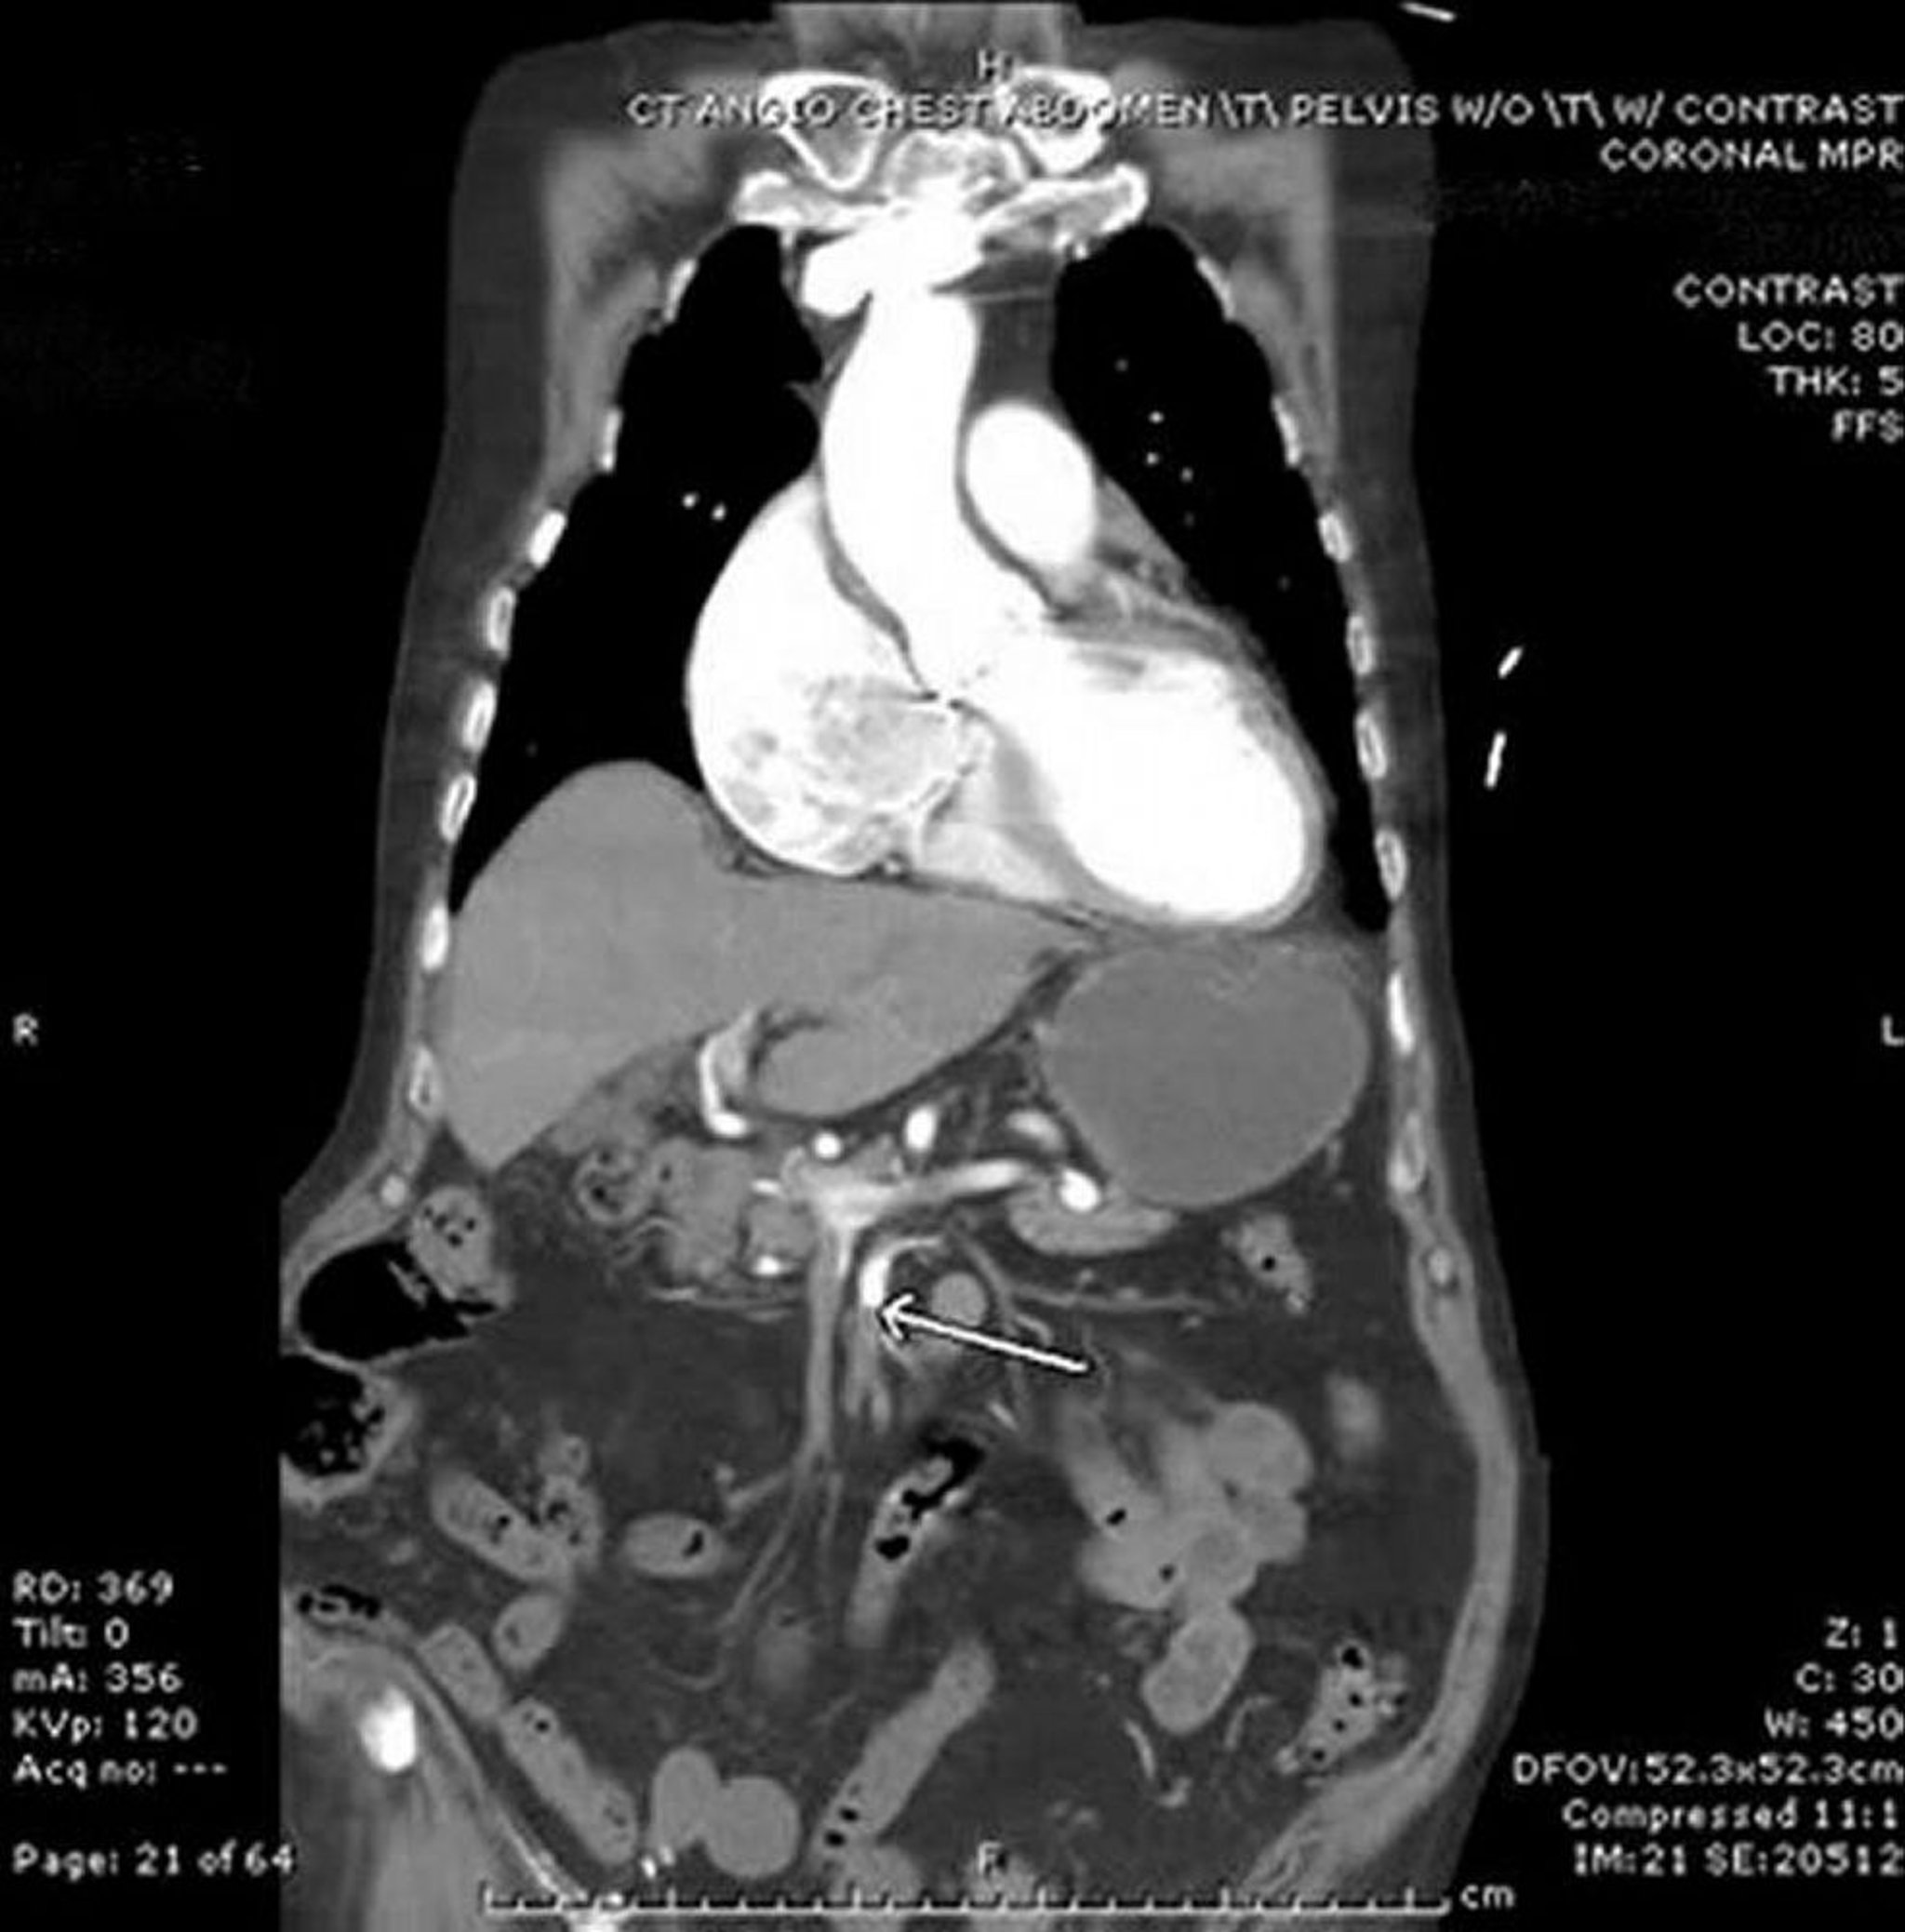

Thiếu máu cục bộ mạc treo (chụp mạch CT)

Trong hình ảnh này, mũi tên chỉ vào động mạch mạc treo tràng trên, nơi có điểm cắt đột ngột của thuốc cản quang đường tĩnh mạch. Thấy thành ruột non ở bụng trái hơi dày lên. Trường hợp thuyên tắc này là từ tim trên một bệnh nhân rung nhĩ.

Hình ảnh do bác sĩ Parswa Ansari cung cấp